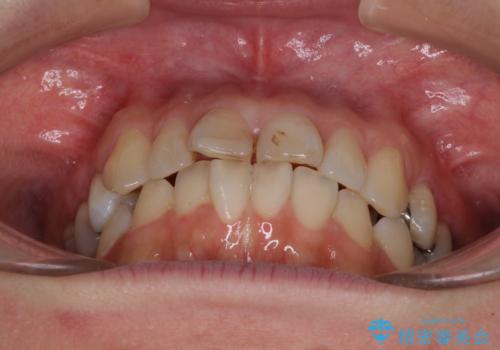

【モニター】前歯のデコボコを治したい インビザラインを用いた矯正治療

- 前歯のデコボコを治したいとのことで来院された患者様です。

上下顎ともに歯列全体の後方移動とIPR(歯と歯の間を削る)によってデコボコが解消するように設計し、インビザラインにより治療を行うこととしました。

しっかりと装着時間を守ってくださったのですが、途中妊娠にともなう悪阻や出産といったイベントがあり、予定よりも治療期間が長くなりました。